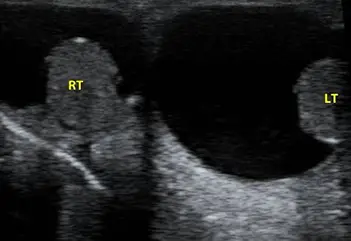

下圖為陰囊的超音波影像,最有可能的診斷為:

題目提供一張對比左右側陰囊(Scrotum)的超音波影像:

- 右側陰囊(RT):睪丸呈現均勻的中等回音(medium echogenicity),外觀與質地正常,周圍僅有極少量或生理性的液體。

- 左側陰囊(LT):左側睪丸本身的回音質地看似正常,但其周圍被大量且大範圍的「無回音(anechoic)」區域所包圍。這個深黑色的無回音區代表液體積聚,且液體均勻地包覆在睪丸周圍(位於睪丸鞘膜的壁層與臟層之間)。睪丸看似懸浮或被擠在該液體積聚區的一側。

- 綜合判讀:左側陰囊出現大量異常的純水液體包覆睪丸,為典型「睪丸鞘膜積液(Hydrocele)」的超音波特徵。